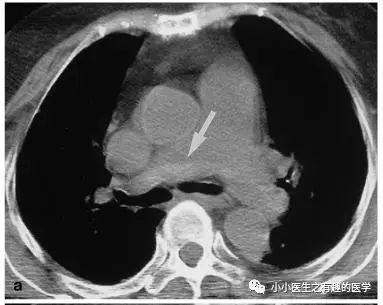

如图,高密度影的那一条。

不怕,有增强CT证实。

是不是很有趣。